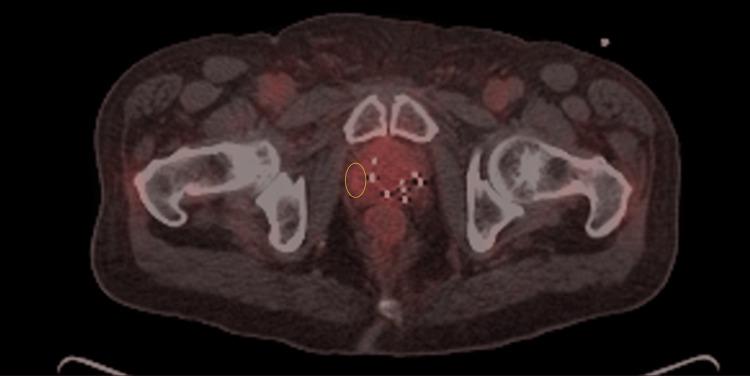

Locally recurrent prostate cancer after radiotherapy is a difficult clinical scenario. Focal therapy with stereotactic body radiation therapy (SBRT) is a promising treatment option. In this case report, we present the case of a male patient who underwent low dose rate (LDR) brachytherapy many years ago and experienced a prostate-specific membrane antigen positron emission tomography (PSMA PET) avid local recurrence of prostate cancer with rising prostate-specific antigen (PSA). He was able to undergo salvage CyberKnife (Accuray, Madison, WI) robotic radiosurgery without the need for additional fiducial marker placement by tracking previously implanted brachytherapy seeds. Treatment of 40 Gy in five fractions to the PET avid tumor gross tumor volume (GTV) and 35 Gy in five fractions to the planning target volume (PTV) was successfully delivered with minimal toxicity. The patient tolerated therapy well with excellent urinary and sexual functioning and declining PSA at the last follow-up.

放疗后局部复发性前列腺癌是一种棘手的临床情况。立体定向体部放射治疗(SBRT)聚焦治疗是一种有前景的治疗选择。在本病例报告中,我们介绍了一名男性患者的病例,该患者多年前接受了低剂量率(LDR)近距离放射治疗,现出现前列腺特异性膜抗原正电子发射断层扫描(PSMA PET)显示前列腺癌局部复发且前列腺特异性抗原(PSA)升高。通过追踪先前植入的近距离放射治疗种子,他能够接受挽救性射波刀(Accuray,麦迪逊,威斯康星州)机器人放射外科手术,而无需额外放置基准标记物。以最小的毒性成功地对PET显示的肿瘤大体肿瘤体积(GTV)分五次于每次8 Gy给予40 Gy的治疗,对计划靶体积(PTV)分五次于每次7 Gy给予35 Gy的治疗。患者对治疗耐受性良好,泌尿和性功能良好,在最后一次随访时PSA下降。